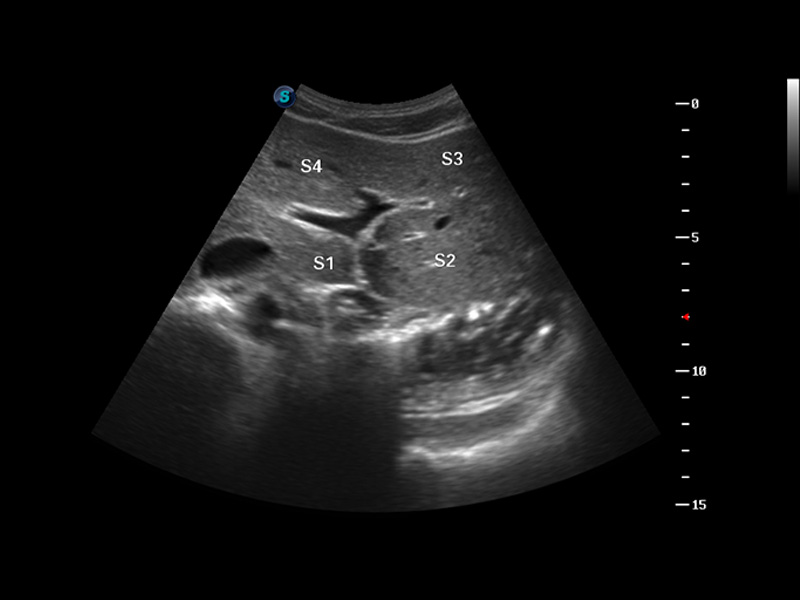

S8 EXP便携式彩色多普勒超声诊断仪是db真人体育官网研发的高端全身应用型便携彩超。高通道的VIS平台融合可视化(Visual)、智能化(Intelligent)和人性化(Smart)的特点,配以db真人体育官网自主研发生产的探头大家族,使您能够快速、准确的获得病人信息,提高工作效率的同时减轻疲劳。

μ-Scan微米成像